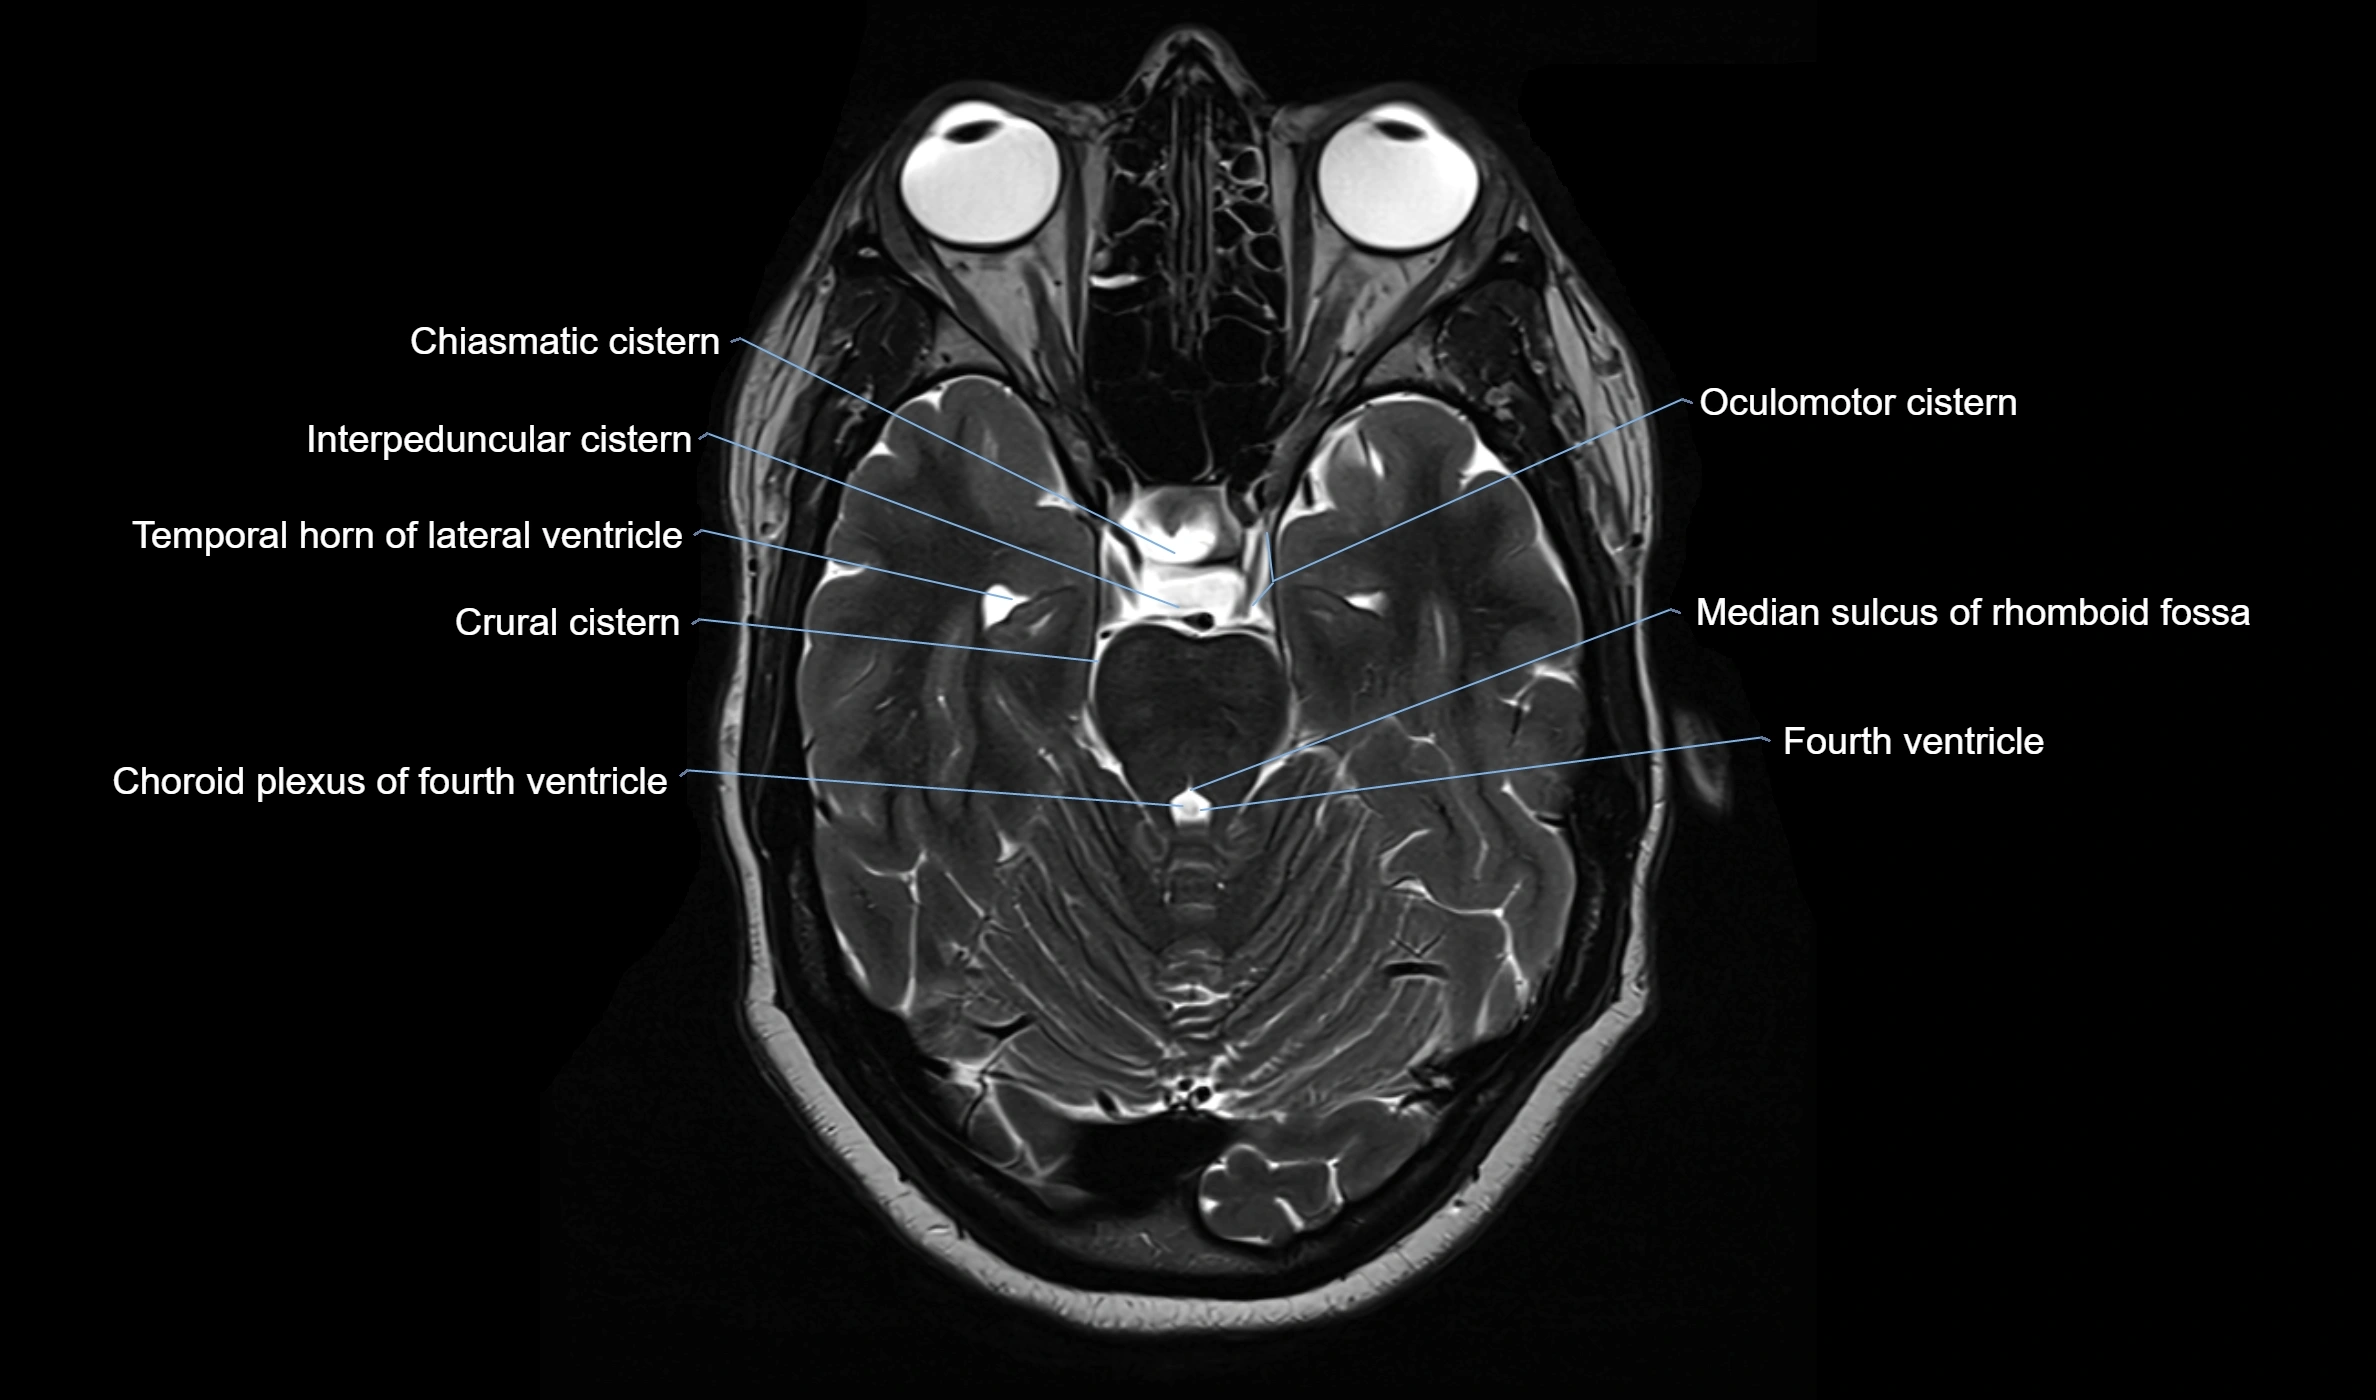

The ambient cistern is a paired, narrow, and elongated subarachnoid space located bilaterally along the lateral aspect of the midbrain. It serves as a conduit between the interpeduncular cistern anteriorly and the quadrigeminal cistern posteriorly. This cistern houses critical neurovascular structures, including parts of the posterior cerebral artery, superior cerebellar artery, trochlear nerve (cranial nerve IV), and the basal vein of Rosenthal. It plays an important role in the circulation of cerebrospinal fluid (CSF) and provides an anatomical corridor for various vessels and nerves passing around the midbrain.

MRI Appearance

• T1-weighted images:

• The ambient cistern appears as a region of low signal intensity, matching the dark appearance of CSF.

• Neurovascular structures within the cistern may appear as flow voids (signal loss from flowing blood) or as small dark linear structures.

• T2-weighted images:

• The cistern is hyperintense (bright) due to the high water content of CSF.

• Encapsulated vessels and nerves are seen as flow voids or hypointense lines within the bright background.